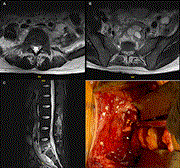

Lumbar and sacral brucellosis due to queso fresco ingestion

Cassandra Krause and others

Journal of Surgical Case Reports, Volume 2021, Issue 2, February 2021, rjaa577, https://doi.org/10.1093/jscr/rjaa577